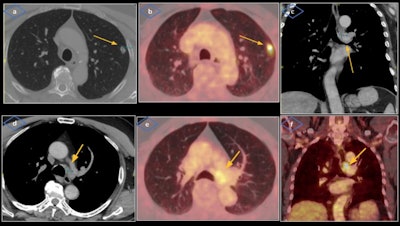

It's necessary to become familiar with the anatomic laryngeal landmarks, pathways of vagus and recurrent laryngeal nerves, CT features of vocal cord paralysis, and causes of recurrent laryngeal nerve paralysis, according to Dr. Alejandra Micolich Vergara and colleagues at Hospital del Mar in Barcelona. "The challenge consists of developing a keen-sighted approach to early detection of VCP and the importance of looking below the clavicles for potential causes."

The cross-sectional imaging modality of choice is contrast-enhanced CT, and PET/CT may also have a role. The CT exam must include the upper mediastinum up to the aortopulmonary window and the scan should be acquired during a period of quiet respiration, so the cords are in an abducted position, the authors added.

"The vagus and recurrent laryngeal nerves cannot be directly visualized on CT; therefore, it is imperative for radiologists to recognize their expected courses so we don't miss out on pathologies that may have more significance than the VCP itself," they pointed out.